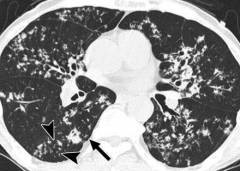

| Компьютерная томография (КТ) легких | Более детальная визуализация фиброзных изменений, “сотового легкого”, бронхоэктазов. | Позволяет уточнить характер и степень выраженности пневмосклероза, выявить осложнения. |

Рентгенография

Рентгенография является одним из ключевых методов для диагностики пневмосклероза. Процедура выполняется с использованием рентгеновского аппарата — устройства, которое преобразует электрическую энергию, поступающую от источника питания, в рентгеновское излучение. Приемником этого излучения служит рентгеновская пленка, на которую попадают лучи после прохождения через тело пациента.

Способность рентгеновских лучей проникать через ткани зависит от их химического состава и структуры легких. То есть, некоторые компоненты легочной ткани, такие как ребра, фиброзная ткань и сосуды, поглощают излучение более интенсивно, чем другие, например, альвеолы и бронхи. Это наблюдается как в норме, так и при различных заболеваниях, включая пневмосклероз. В результате, интенсивность излучения до и после прохождения через грудную клетку будет различаться. Когда рентгеновское излучение попадает на пленку, оно создает уникальный рисунок благодаря фотохимическому эффекту. Таким образом, рентгенограмма представляет собой плоское изображение трехмерной структуры грудной клетки. Светлые участки на пленке обозначают области затемнения, а черные — просветления. Чем больше затемнение, тем сильнее оно поглощает излучение, и наоборот.

Во время рентгенографии пациента располагают между рентгеновской трубкой и кассетой, при этом грудная клетка должна плотно соприкасаться с кассетой. Расстояние между трубкой и пациентом составляет от 60 до 100 см. Рентгенография может быть как прицельной, так и обзорной. Существует два основных типа проекции: прямая (пациент стоит лицом или спиной к пленке) и боковая. В целом, процедура занимает от 1 до 5 минут. Обычно результаты становятся доступны на следующий день, так как пленка требует обработки в фотолаборатории. На современных аппаратах изображение может быть получено гораздо быстрее в цифровом формате.

Признаки пневмосклероза на рентгенограмме включают:

- Затемнение в легких. Оно может варьироваться по площади и интенсивности. Например, при циррозе затемнение будет очень выраженным, тогда как на ранних стадиях фиброза — едва заметным. Полное затемнение указывает на наличие склероза во всем легком, субтотальное — в одной из долей, а ограниченное — в конкретном сегменте.

- Изменение легочного рисунка. Легочный рисунок представляет собой кровеносные сосуды, которые контрастируют на фоне легочных альвеол, бронхов и соединительнотканных прослоек. При пневмосклерозе наблюдается выделение этих структур из-за разрастания фиброзной ткани вдоль сосудов, бронхов и других анатомических образований.

- Уменьшение размера легкого. Если пневмосклероз затрагивает только одно легкое, оно будет меньше по сравнению с другим. Это связано с тем, что в пораженный участок поступает меньше воздуха, а его эластичность ограничена.

- Смещение средостения. На рентгенограмме средостение выглядит как неравномерное затемнение, расположенное в центре снимка, за грудиной. Если одно из легких уменьшилось в объеме из-за пневмосклероза, тень средостения будет смещена в сторону пораженного легкого.

Компьютерная и магнитно-резонансная томография

Данные методы исследования являются весьма информативными при пневмосклерозе, но используются довольно редко из-за высокой стоимости процедуры. КТ представляет собой серию рентгенографических снимков высокого качества, которые позволяют выявить даже небольшие образования в легких. МРТ предполагает получение трехмерного изображения легких с помощью мощного магнитного поля (регистрируется движение заряженных частиц в тканях ). Эти методы способны обнаружить при пневмосклерозе мелкие очаги разрастания соединительной ткани или начинающееся утолщение стенок сосудов (альвеол, бронхиол и т. п. ) на ранних стадиях болезни. КТ и МРТ используются в основном для обследования больных, у которых причина развития пневмосклероза не ясна. Также их назначают иногда перед оперативным вмешательством (в случае травм грудной клетки, при аномалиях развития легких ) для уточнения локализации патологического процесса.